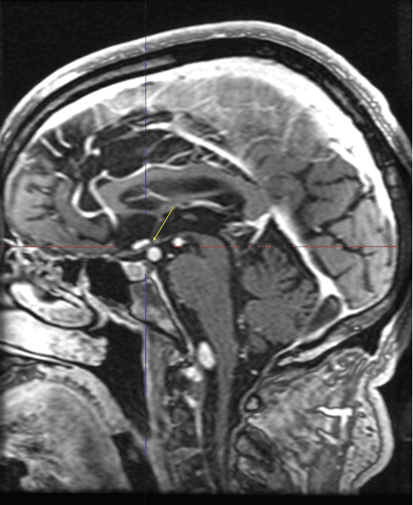

Visual field testing revealed a progressed visual field defect respecting the vertical midline consistent with a right hemianopsia (Figure 3). These visual field findings prompted obtaining MRI/MRA, which revealed dolichoectasia of the vertebrobasilar system with mass effect on the left optic tract at the level of the posterior cerebral artery (PCA) origins (Figure 4).

Figure 4. MRI/MRA results revealed (left) dolichoectasia of the vertebrobasilar system with mass effect on the left optic tract at the level of the posterior cerebral artery (PCA) origins